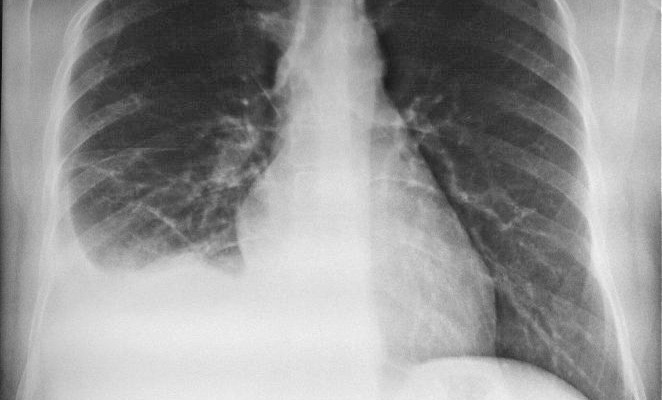

Чаще всего в практике встречается рентгенография грудной клетки, вариант которой (флюорографию) взрослый человек должен проходить раз в год. На получаемых снимках, вопреки заблуждениям, изучается не только состояние лёгких. Рентгенологи описывают как внешние костные структуры, так и содержимое грудной клетки. Поэтому одним снимком можно не только исключить одно заболевание, но и выявить совершенно другое.

- Начинается диагностика с оценки состояния лёгочной ткани – она производится поочерёдно в каждом промежутке между рёбрами с правой и левой стороны. В норме этот орган практически не виден на рентгенограмме, что объясняется большим содержанием в нём воздуха. Поэтому излучение быстро проходит его, практически не оставляя следов на плёнке.

При осмотре симметричных лёгочных полей в первую очередь учитывается их однородность. Если всё же подозревается какое-либо отклонение, то его сравнивают только с аналогичным участком другого лёгкого. Чаще всего при патологии встречаются следующие изменения:

- Затемнения представляют собой очаг уплотнённой ткани, в котором отсутствует воздух. Несмотря на название, на рентгенограмме они определяются как светлые пятна разнообразных форм и размеров. Чаще всего они наблюдаются при воспалительных заболеваниях – пневмониях.

- Аналогичным симптомом характеризуются опухоли – им ещё присуще формирование лучистости. Такое затемнение будет иметь чёткий наружный контур, от которого к внутренней поверхности лёгкого будут отходить тонкие светлые лучи.

- Изменение лёгочного рисунка проявляется как утрата однородности – на фоне тёмных полей между рёбрами будут наблюдаться упорядоченные или хаотичные светлые полосы.

- Корни лёгких могут быть расширены – при этом светлые пучки резко утолщаются, нередко занимая всю внутреннюю поверхность лёгких. Такие изменения возникают при различных воспалительных процессах, поражающих бронхи и лимфатические узлы.

Большинство рентгенологических симптомов описано именно относительно заболеваний лёгких, что ставит этот метод исследования на первое место в диагностике патологии органов дыхания.